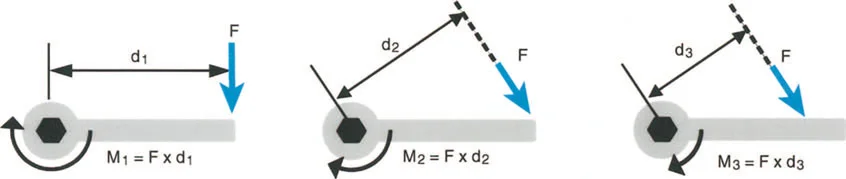

يشير خلل وظيفة الذراع الرافعة إلى التغيير المرضي في علاقات الرافعة الطبيعية بين ثلاثة مكونات حاسمة:

1. الحمل (The Load): الوزن أو المقاومة التي يجب التغلب عليها.

2. الجهد (The Effort): القوة العضلية المطبقة لتحريك الحمل.

3. موضع نقطة الارتكاز (The Fulcrum Position): المفصل الذي يحدث حوله الدوران.

بشكل خاص، يصف خلل وظيفة الذراع الرافعة حالة سريرية تتشوه فيها أذرع الرافعة الداخلية و/أو الخارجية بسبب سوء محاذاة العظام، أو التشوهات الالتوائية، أو تيبسات المفاصل الموضعية.

تاريخياً، كان جراحو العظام بطيئين في إدراك الأهمية القصوى لخلل وظيفة الذراع الرافعة، وغالبًا ما كانوا يركزون فقط على تحرير الأنسجة الرخوة أو نقل الأوتار. غالبًا ما يؤكد التدريب الجراحي على التفكير في العضلات على أنها مجرد مولدات طاقة بيولوجية. ومع ذلك، فإنه قانون أساسي في الفيزياء أن الطاقة لا يمكن توليدها أو نقلها أو استخدامها دون الاستفادة من أذرع الرافعة الهيكلية التي تتصل بها تلك العضلات.

بمجرد أن يبدأ الجراح في التفكير من حيث "العزوم" التي تولد القوة، بدلاً من مجرد انقباض عضلي معزول، فإنه يبدأ تلقائيًا في فحص النصف الآخر من المعادلة الميكانيكية: الرافعة نفسها.

بينما لا يستطيع الطب الحديث فعل الكثير لزيادة القوة البيولوجية الخام التي تولدها العضلة بشكل دائم (بخلاف العلاج الطبيعي)، يمكن غالبًا زيادة حجم العزم المؤثر على المفصل بشكل كبير ببساطة عن طريق تصحيح خلل وظيفة الذراع الرافعة جراحيًا. هذا هو جوهر النهج الذي يتبعه الأستاذ الدكتور محمد هطيف في علاج التشوهات العظمية المعقدة، حيث يركز على استعادة الميكانيكا الحيوية السليمة للجسم.